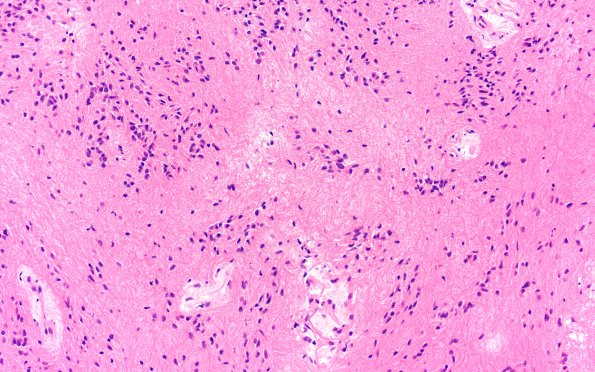

Subependymoma

18B5 Subependymoma (Case 18) H&E 20X 4

The neoplasm shows clusters of nuclei in a fibrillary background. (H&E)